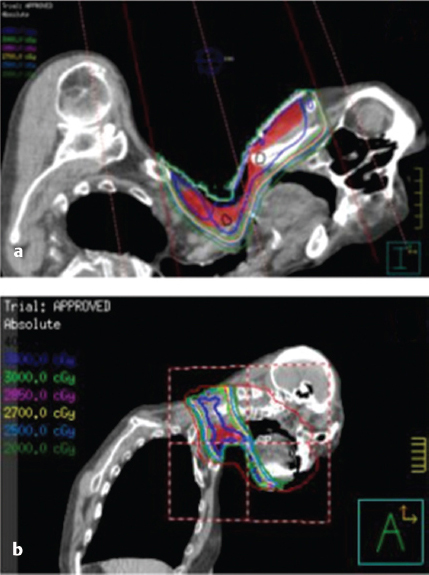

7 Role of Radiotherapy in the Treatment of Skin Malignancies Non-melanomatous skin cancers (NMSC), specifically basal cell carcinoma (BCC) and squamous cell carcinoma (SCC), are the most common malignancies in the United States. They are primarily managed surgically and carry an excellent prognosis, with a 1 to 5% rate of disease recurrence after complete excision and only exceedingly rare instances of distant metastasis. Historically, radiotherapy played a prominent role in the definitive management of these cancers as an alternative to surgical resection, especially in cosmetically sensitive areas. With the improvement in surgical techniques in recent decades, especially the widespread use of Mohs micrographic surgery (MMS), the use of curative radiation for skin cancers has declined. However, radiation is still commonly used in the definitive setting for patients with NMSC who are poor surgical candidates or have larger lesions in cosmetically sensitive regions of the face, and in the postoperative setting for more advanced tumors that have high-risk pathologic features that are associated with excessive risks of locoregional recurrence after surgery alone. Radiotherapy plays a similar role in the postoperative management of cutaneous melanoma. Radiation also offers excellent palliation for noncurable patients. This chapter reviews common indications, dose and fractionation schedules, techniques, and oncologic and cosmetic outcomes for radiotherapy for NMSC and melanoma ( Both surgery and RT can offer excellent cure rates for the management of early-stage NMSC. Surgery is typically the preferred method of treatment, given it can be performed in a single session, and has been associated with superior oncologic and cosmetic outcomes. One prospective randomized study compared the outcomes of MMS and definitive RT in 347 patients with less than 4 cm BCC of the face. The local failure rate was 0.7% for patients treated with MMS and 7.5% for patients treated with RT. Additionally, the cosmetic outcome was rated “good” or better more often in those patients who underwent surgery (87 vs. 69%).1 Though the technique of RT was not controlled (55% received interstitial brachytherapy and 45% received orthovoltage therapy), which could have affected the quality of the comparison, as the only randomized study, this trial remains pivotal in guiding medical decision making. A variety of factors can influence the decision to favor RT rather than surgery for NMSC. Typical contraindications to definitive RT include very large tumors and those with bone and/or cartilage invasion, given that control rates are typically inferior, as well as recurrent tumors that have been previously radiated or arise in an area of previous radiotherapy. Radiation should also be avoided in patients with genetic radiosensitivity syndromes, such as xeroderma pigmentosum and basal cell nevus syndrome, and in those with active connective tissue diseases, such as scleroderma and systemic lupus erythematosus.2 Patients who are candidates for definitive RT include those with unresectable disease, older patients with comorbidities limiting their surgical options, and patients with lesions involving the eyelid, canthi of the eye (especially those who carry surgical risk to the lacrimal duct), external ear ( Fig. 7.1 A modern linear accelerator, capable of delivering photon and electron radiotherapy with image guidance provided by cone beam CT (red arrow). A robust literature, much of it older when RT was more commonly used, supports the safety and efficacy of definitive RT for many of these aforementioned types of patients. A review of 986 BCC and SCC of the skin overlying the eyelid treated with definitive RT demonstrated a 5-year cure rate of 96.4%.3 A review of 334 BCC and SCC of the external ear at the Princess Margaret Hospital treated with definitive RT demonstrated a 2-year local control rate of 87%, with severe late toxicity noted in only 7% of patients.4 A review of 100 patients with SCC of the nasal skin at the Princess Margaret Hospital treated with definitive RT demonstrated a 2-year local control rate of 90%, with no severe toxicities observed.5 Fig. 7.2 (a) SCC of the helix of the left ear with bleeding (baseline). (b) After treatment with definitive radiation therapy (50 Gy in 20 fractions with electrons). There was complete remission with excellent cosmesis. Fig. 7.3 (a) A 96-year-old patient with right retroauricular BCC, T2N0M0 (baseline). (b) One month after treatment with definitive radiation therapy (50 Gy in 20 fractions with electrons). While definitive RT monotherapy can provide effective tumor control for T1–3N0 NMSC, T4 tumors and those with nodal metastases demonstrate inferior outcomes. Initial surgical management is recommended in these patients, often followed by adjuvant radiotherapy. T4 disease is defined as tumor invasion into the axial or appendicular skeleton or perineural invasion (PNI) of the skull base. The University of Florida reported a local control rate of just 53% at 5 years in patients with T4 BCC and SCC.6,7 In a review of 68 T4 BCC and SCC of the skin of the head and neck treated with definitive RT, local control rates were lower in patients with recurrent disease, compared to primary lesions (41 vs. 67%; p = 0.07) and the three most important prognostic indicators for inferior local control and cause-specific survival rates were bone involvement (p < 0.01), recurrent lesions (p < 0.01), and nerve involvement (p < 0.02).6 Even the more favorable lesions had local control rates of less than 70%. Similarly, a large retrospective review which included 531 BCC and SCC treated with definitive RT demonstrated local control rates of 94 and 89% for primary BCC and SCC tumors, respectively, and 86 and 68% for BCC and SCC recurrent tumors, respectively.8 In patients with nodal metastases, locoregional recurrence rates with definitive RT alone range from 30 to 50% and cancer-related mortality is as high as 30%.9 Such suboptimal outcomes support the use of intensification of treatment and multimodal therapy for these patients with advanced disease. In patients who are not eligible for initial surgical resection, concurrent cisplatin-based chemotherapy can be considered to enhance the effectiveness of radiotherapy. While there is no high-quality evidence demonstrating clear benefit to such an approach in cutaneous malignancies, many head and neck oncologists extrapolate from the mucosal SCC of the head and neck, where concurrent chemotherapy significantly improves disease control and survival in the setting of locally advanced disease treated nonoperatively.10 Fig. 7.5 A patient with multifocal BCC 3 months after treatment with definitive radiation therapy (40 Gy in 10 fractions with electrons). Postoperative RT is rarely used for BCC. Patients with BCC have an exceedingly low risk of recurrence after surgery alone, and even patients with a positive margin, focal cartilage invasion, or PNI are often still candidates for close observation and salvage re-resection if needed.11,12 However, postoperative RT is often considered in cases where there are persistently positive margins after multiple resections, T4 disease that extensively invades bone or soft tissue, lymph node metastasis, or clinically apparent PNI ( Postoperative RT is much more commonly used in resected SCC ( Retrospective data have demonstrated high rates of local recurrence in patients with T4 tumors managed with surgery alone.7 In addition, the rate of occult lymph node metastasis is high, ranging from 29 to 50%, in patients with advanced T-stage disease. In patients with deeply infiltrative (≥ 8 mm) tumors, or tumors that extensively invade deep subcutaneous fat, occult lymph node metastasis can be as high as 30%.9 Patients with recurrent primary tumors, PNI, lymphovascular space invasion, and those that are immunosuppressed are at significantly higher risk for having lymph node metastases and should undergo careful evaluation for regional disease with a contrast-enhanced diagnostic neck computed tomography (CT) and/or a positron emission tomography scan.14,15,16 In these patients, sentinel lymph node biopsy and/or neck dissection is recommended in conjunction with resection of the primary tumor. Postoperative RT can also be useful as an elective treatment to the undissected neck. Fig. 7.6 (a) A patient with right brow/forehead SCC (baseline). (b) One month after definitive radiation therapy (45 Gy in 15 fractions with electrons). Fig. 7.7 (a) An 88-year-old man with left temporal SCC in situ (baseline). (b) One month after treatment with definitive radiation therapy (30 Gy in five fractions with electrons). For patients with clinically involved lymph nodes, a therapeutic neck dissection followed by postoperative RT is the current standard of care. Although lymph node metastases are rare in SCC of the skin overall (~ 5%), they are clearly associated with a poor prognosis. After neck dissection alone, locoregional recurrence rates are 11 to 38% and even after multimodality therapy, the 5-year disease-free survival rates are 60 to 70%. Independent predictors of worse survival in this population include increased nodal size ≥ 3 cm, multiple lymph node involvement, extracapsular extension, incompletely excised nodes, and surgery monotherapy.15,16,17 A review of 167 patients in Australia with SCC metastatic to the parotid or cervical nodes compared outcomes for surgery versus combination of surgery and postoperative RT at a median dose of 60 Gy in 30 fractions. The use of postoperative RT was associated with significantly lower rates of locoregional recurrence (20 vs. 43%), and higher 5-year disease free (73 vs. 54%; p = 0.004), and 5-year overall survival (66 vs. 27%; p = 0.003) compared to patients who received surgery alone.16 Similar results supporting the benefit of postoperative RT for locoregional control and 5-year disease-free survival in patients with cutaneous SCC metastatic to lymph nodes and/or periparotid lymph nodes have been reproduced in a number of retrospective reviews.18,19,20,21 For patients who received lymph node dissection for primary SCC located on the trunk or extremities, postoperative RT is typically recommended when multiple nodes are involved or extracapsular extension is present. Similar to mucosal SCC of the head and neck, RT can be avoided in immunocompetent patients with a single involved lymph node, smaller than 3 cm, without extracapsular extension on parotidectomy or cervical lymph node dissection, as rate of regional recurrence is less than 5%.22 Fig. 7.9 A 91-year-old man with a history of extreme kyphosis and multiple facial SCC, who presented with a rapidly enlarging right neck mass, treated with surgical resection and free flap reconstruction. (a) Axial slice depicting isodose coverage of the neck bed with electron radiation therapy. (b) Extreme kyphosis dose coverage using 30 Gy in five fractions twice weekly. Fig. 7.10 A 63-year-old man with multiple recurrent SCC of the right temple with Mohs map overlying the site of the tumor. Fig. 7.11 (a) Coronal CT slice of dose distribution for postoperative radiation therapy after Mohs surgery for tumor depicted in PNI, while not common (5–10% of SCC), is another important risk factor for recurrence that should be weighed in the decision to administer adjuvant RT. PNI is typically divided into clinical and microscopic PNI. Clinical PNI is defined by neurologic manifestations, most commonly involving the trigeminal or facial nerves, leading to pain, paresthesias, paralysis, formication (the sensation of bugs crawling on the skin), or radiographic evidence of nerve enhancement.23,24 Microscopic PNI is appreciated only histologically and is identified after surgery in a patient who was asymptomatic preoperatively. PNI is important given it is associated with increased risks of local recurrence as well as regional and distant metastases. Factors associated with increased risk for SCC with PNI include male sex, tumor size greater than 2 cm, midfacial tumor location, recurrent tumor, and poorly differentiated subtypes.25 The degree of PNI is predictive of risk of recurrence; therefore, a careful history as well as physical and imaging examination is critical. Magnetic resonance imaging (MRI) has the advantage of identifying the extent of macroscopic disease through nerve enlargement or enhancement or obliteration of the normal fat plane surrounding a nerve ( The difference between clinical and microscopic PNI was highlighted in a series from the University of Florida which compared the outcomes of patients with PNI treated aggressively with surgery and postoperative RT. Those with clinical PNI had significantly lower 5-year rates of local control (57 vs. 90%; p = < 0.001) and overall survival (57 vs. 69%; p = 0.03) compared to those found to have microscopic PNI.13,23 RT is therefore always recommended in cases of clinical PNI. The role of postoperative RT in patients with pathologic PNI is less clear. Lin et al found that focal versus extensive microscopic PNI carries different prognoses, with relapse-free survival better in the former group (86 vs. 74%; p =0.1).24 Unfortunately, the distinction between focal and extensive was not well defined. As such, adjuvant RT is not recommended in immunocompetent patients with nonrecurrent disease, in whom one or two isolated areas of PNI are found in small unnamed nerves, with a diameter of less than 0.1 mm, given the outcome is expected to be fairly good with surgery alone. However, patients with microscopic PNI, that is multifocal, involves larger nerves (> 0.1 mm in diameter) and named nerves, or occurs in immunosuppressed patients, are at higher risk and thus adjuvant RT is recommended.2,25 For irradiation of clinical PNI, the clinical target volume should include areas at high risk of failure, specifically the involved nerve, the portion of the nerve proximally at the skull base, the distal skin innervated by the nerve, major communicating branches, and the compartment in which the nerve is embedded.26 For example, for patients with CN VII involvement, the area of treatment should be tracked back to the nerve’s exit through the stylomastoid foramen, with care taken to administer adequate coverage of the geniculate ganglion by avoiding excessive restriction of the radiation dose delivered to the ipsilateral cochlea. Similarly, with V1/V2 nerve involvement, the gasserian ganglion in Meckel cave and the cavernous sinus should be targeted ( Another consideration highly relevant to radiation field design is the observation that PNI may also be associated with increased nodal failure in addition to recurrence in the tumor bed and along the nerve pathway. Lin et al demonstrated that patients who developed recurrent disease with pathologic PNI had a significantly higher risk of local recurrence (40 vs. 19%; p < 0.01) as well as regional recurrence (29 vs. 5%; p = 0.02).24 It is important to consider the location of the lesion in such scenarios, given that tumors on the scalp, for example, may be less likely to metastasize to lymph nodes, compared to cheek, ear, or nasal skin lesions. Understanding the drainage patterns of these tumors is crucial (e.g., parotid nodes for head and neck sites, axilla for trunk and extremity lesions) and should be incorporated into radiation targeting. Fig. 7.13 (a) Axial radiation planning CT slice depicting inferior alveolar nerve (solid red) covered by isodose lines. (b) Axial radiation planning CT slice depicting left cavernous sinus and temporal musculature (solid light blue) covered by isodose lines. (c) Axial radiation planning CT slice depicting course of V2 into cavernous sinus (solid red) covered by isodose lines. (d) Sagittal radiation planning CT slice depicting coverage of V1 and V2 back to the cavernous sinus (solid red) covered by isodose lines. Fig. 7.14 (a) A 67-year-old man with history of recurrent right auricular SCC treated with multiple surgical resections and prior irradiation who presented with recurrent disease at the right skull base (red arrow). (b) Sagittal radiation planning CT slice depicting recurrent disease covered by 70 Gy isodose line (black line). Melanoma is believed to be a relatively radioresistant malignancy. Therefore, maximal surgical resection is paramount in the management of these tumors. RT has limited benefit in achieving long-term control in the presence of gross disease. RT is delivered to gross melanoma in patients deemed to have unresectable disease, or those with rapid postoperative recurrence who have failed surgical management. In these cases, higher doses per fraction are generally preferable and the intent of treatment is largely palliative. Adjuvant radiotherapy to the primary tumor bed, nodal basin, or both, has been studied as a means of reducing locoregional recurrence. If adequate margins are obtained, local recurrence for primary melanoma is infrequent, with rates consistently reported to be less than 5%.27,28 However, there is a smaller subset of patients with higher rates of failure in the tumor bed, including deeply invasive T4 disease, the presence of satellitosis, the presence of desmoplastic subtype, or persistently positive margins despite multiple attempts at excision. In these cases, adjuvant RT to the primary tumor bed should be considered ( O’Brien and colleagues analyzed 629 patients with head and neck melanoma and found that increased local recurrence rates were associated with increased tumor thickness: < 0.76 mm, 2%; 0.76 to 1.49 mm, 5%; 1.5 to 3.99 mm, 15%; and ≥ 4 mm, 20%.29 Typically, adjuvant RT is considered for T4 tumors, although typically reserved for those with additional high-risk features. One of which is satellitosis, which represents discontiguous sites of disease within 2 cm of the primary tumor and is known to be a marker of increased recurrence risk.30 Desmoplastic melanoma is a rare histologic subtype (1% of all melanomas) and is characterized by spindle-shaped cells with associated collagen production. This subtype is often associated with perineural spread and local recurrence rates have been reported as high as 20 to 50%.31,32 In these cases, based on the relatively higher risk for local recurrence, adjuvant RT should be considered. More extensive literature guides the use of adjuvant RT to nodal basins, both in the elective setting and following lymph node dissection.33,34 Data supporting the benefit of RT in reducing regional recurrence come from the randomized phase III study by Burmeister et al in which higher risk patients were randomized to surgery and lymph node dissection with or without adjuvant radiation to the nodal basin.35 Eligible patients had one of the following features associated with increased failure rates: 1. Serum lactate dehydrogenase < 1.5 times the upper limit of normal and the presence of extracapsular extension (ECE). 2. ≥ 1 involved parotid node of any size. 3. ≥ 2 involved cervical nodes and/or ≥ 3 cm of tumor within a node. 4. ≥ 2 involved axillary nodes and/or ≥ 4 cm of tumor within a node. 5. ≥ 3 involved inguinal nodes and/or ≥ 4 cm of tumor within a node, and/or recurrent disease.27,30 Importantly, no systemic therapy was delivered in this trial. In the 217 patients included on the study, those who received RT were significantly less likely to experience regional recurrence compared to those in the observation arm (18 vs. 33%; p = 0.041). As distant metastasis is the predominant mode of melanoma disease failure, it was not surprising that an improved rate of regional control did not translate into an overall survival average (54 vs. 44%; p = 0.12). The most common Grade 3 or 4 adverse events were seroma and wound infections, which were equivalent in both arms.35 The lack of systemic therapy in this study as well as the lack of a survival difference with the use of RT has raised the question of the true benefit of adjuvant RT for all patients eligible for this study. That said, it reinforces the guiding principle where locoregional control is a priority, and in a case with extensive nodal disease, especially with extranodal extension and significant soft-tissue involvement, adjuvant RT should be considered as a proven way to reduce rates of locoregional recurrence ( Fig. 7.15 A 72-year-old man with pT3N2cMx melanoma of the scalp with ulceration and satellitosis treated with wide local excision, free flap reconstruction, ipsilateral neck dissection, and adjuvant RT to the primary tumor bed. (a) Postoperative image. (b) Axial radiation planning CT slice demonstrating bolus material (red arrow) for achieving adequate surface dose.

Fig. 7.13). Targeting the nerve root as it exits the brainstem should be considered for nerves that are radiographically involved at the skull base. For patients with unresectable disease invading the skull base, high-dose radiation (70 Gy), with or without concurrent chemotherapy, is required (

Fig. 7.14).